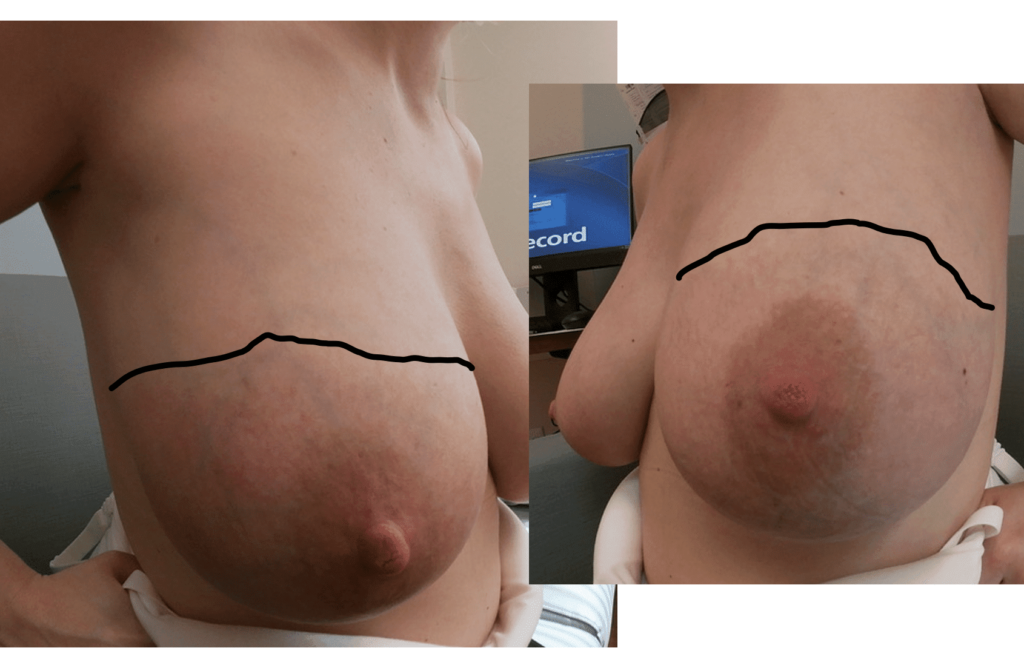

Gigantomastia

Gestational gigantomastia likely represents a spectrum of excessive breast growth during pregnancy. It may include women who grow multiple cup sizes, or those for whom the breast growth is so significant it can cause mobility impairments. Hormonal factors may play a role in gigantomastia, but true cause remains unknown. It also remains unclear whether the growth represents true glandular development or simply fluid retention in the breast as occurs in other parts of the body during pregnancy. Women gigantomastia that is not significant enough to cause skin breakdown but do experience growth do not necessarily produce large volumes of milk.

Photo: Clara Farley

Photo: Clara Farley

Photo: Clara Farley

Photo: Clara Farley

During pregnancy, it is treated by bromocriptine (an anti-prolactin agent) alternating with metformin (modulates insulin). Postpartum, patients should be given bromocriptine or cabergoline (anti-prolactin agent) before lactogenesis II (secretory activation, or “milk coming in”) to reduce the risk of skin necrosis (ulceration and death of skin). Donor milk or formula supplementation should be planned. Patients can later undergo elective breast reduction. The patient above is pictured below at end of pregnancy after being treated with lymphatic drainage and bromocriptine during pregnancy:

Improvement in lymphedema with lymphatic drainage and supportive bra/garment, just before delivery. Photo: Clara Farley, MD

As discussed in the Pregnancy and Birth section, women may experience breast lymphedema (swollen breast) and pain, particularly during periods of early breast growth in the first trimester and in the last trimester nearing childbirth. This is more common than true gigantomastia. This discomfort is related to increase in the gland, blood vessels, and surrounding fluid. Swelling and even pitting usually is most evident in the lower part of the breast, and can be pink or mildly reddish in color. These cases also. can gain significant relief from lymphatic massage and supportive bras. Any asymmetry in presentation warrants referral to a breast surgeon to evaluate for breast masses and/or inflammatory breast cancer.